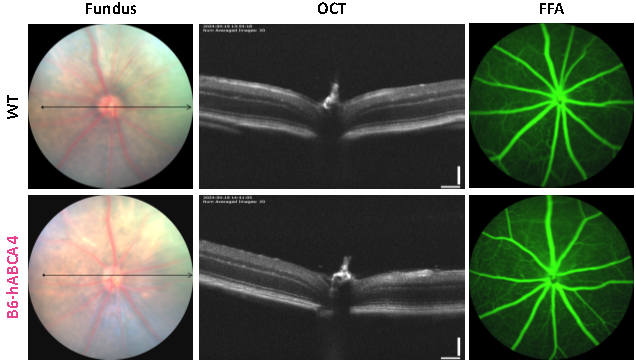

该模型仅表达人类ABCA4基因及其转录本,同时保持正常的视网膜结构和光感受器功能。

图5. B6-hABCA4小鼠成功表达人类ABCA4基因并保持正常的视网膜结构和光感受器功能。